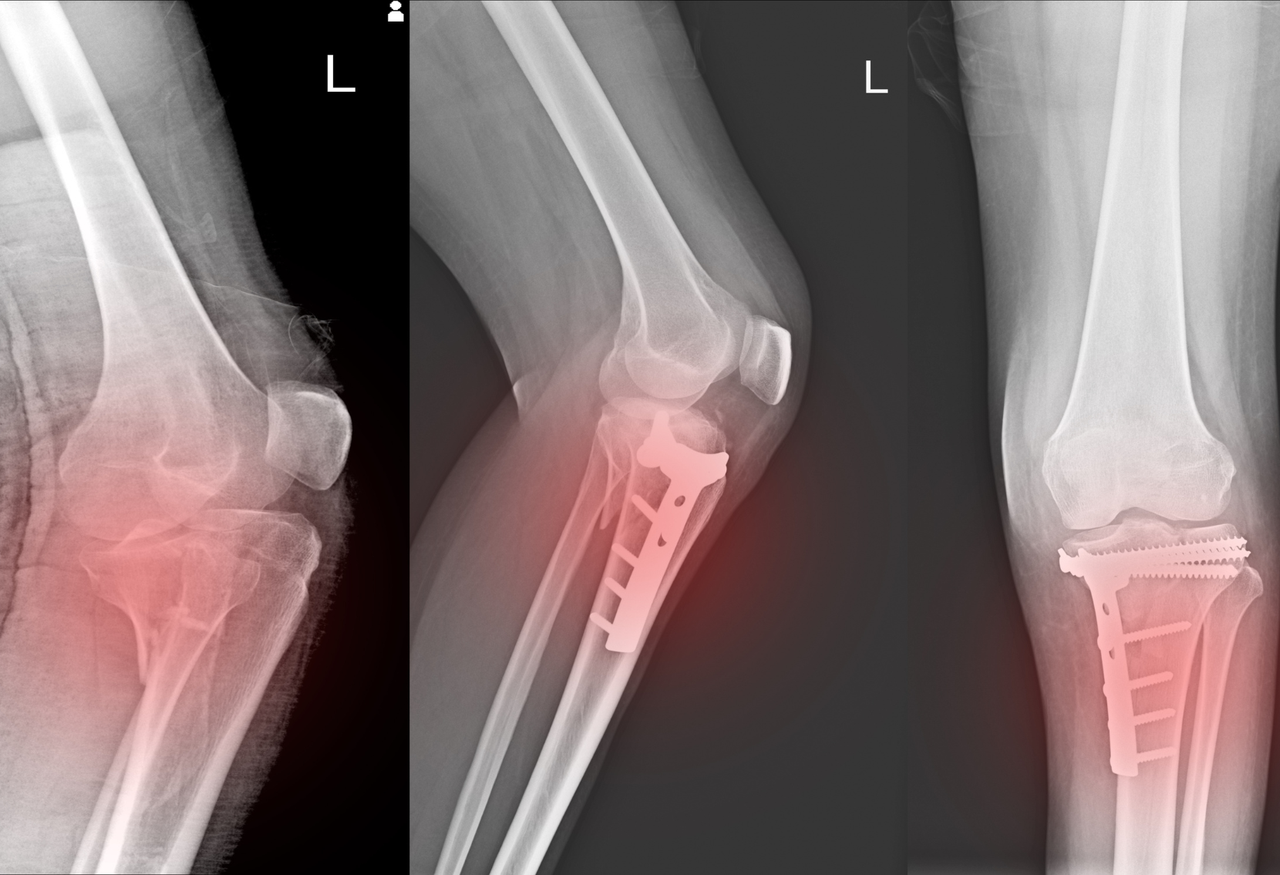

Evaluación y tratamiento de fracturas

Diagnóstico y manejo médico o quirúrgico para una correcta recuperación del hueso.

Cirugía_de_fracturas

Cirugía de fracturas y prótesis articulares.

Procedimientos quirúrgicos destinados a estabilizar y reparar fracturas complejas, así como a reemplazar articulaciones dañadas mediante implantes internos, con el objetivo de aliviar el dolor, restaurar la función y mejorar la movilidad del paciente.